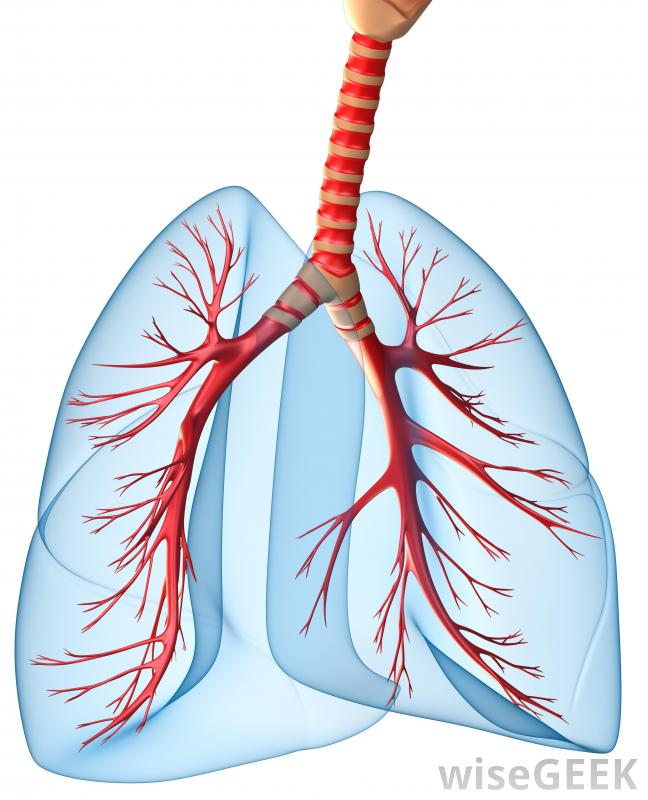

胸膜纤维化是胸膜(覆盖肺部的组织)发展成纤维组织的一种情况。在正常情况下,胸膜是一种非常柔软的粘液膜,但当胸膜纤维化发生时,胸膜变厚变硬。纤维生长是良性的,但如果广泛存在,可能会给患者带来并发症,并且可能与对患者有害...

胸膜纤维化是胸膜(覆盖肺部的组织)发展成纤维组织的一种情况。在正常情况下,胸膜是一种非常柔软的粘液膜,但当胸膜纤维化发生时,胸膜变厚变硬。纤维生长是良性的,但如果广泛存在,可能会给患者带来并发症,并且可能与对患者有害的疾病过程有关。

随着胸膜增厚,肺不得不更加努力地充气,导致呼吸困难。胸膜中也可能出现胸膜钙化和胸膜纤维化钙化,胸膜上出现小的白色斑块。在轻度病例中,这些斑块可能没有问题,但如果它们变大、扩散,或与广泛的胸膜纤维化相关,则可引起关注纤维化也可能发生在脏器周围的粘液膜上,例如心脏和肠道。